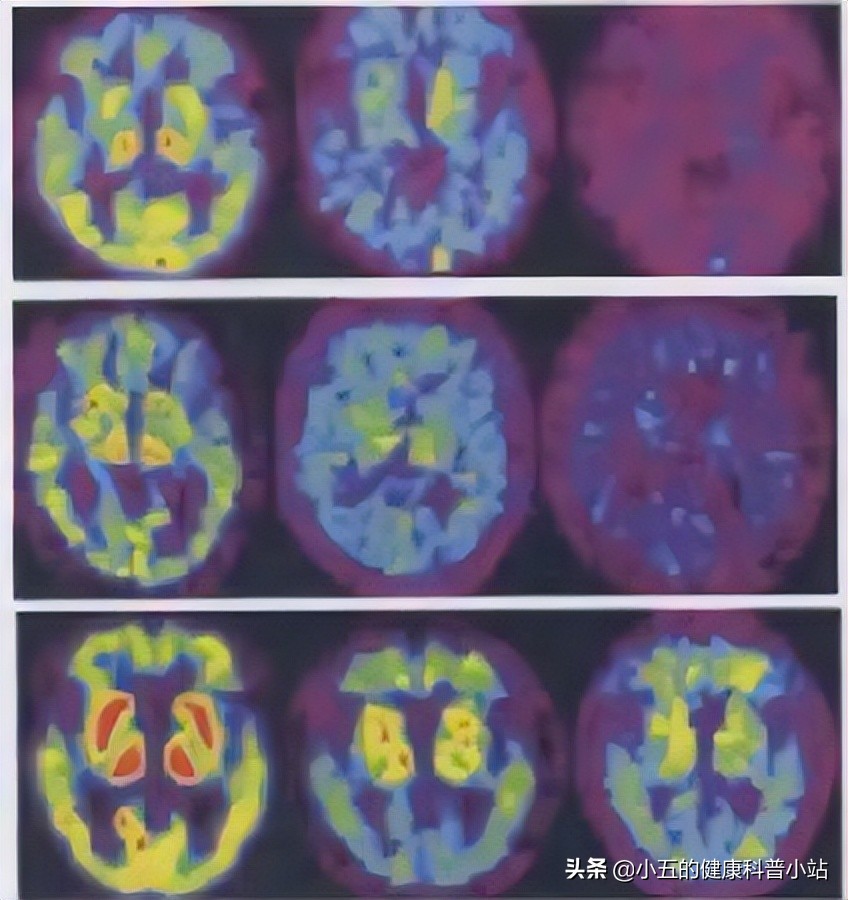

图片来自于网络,侵删